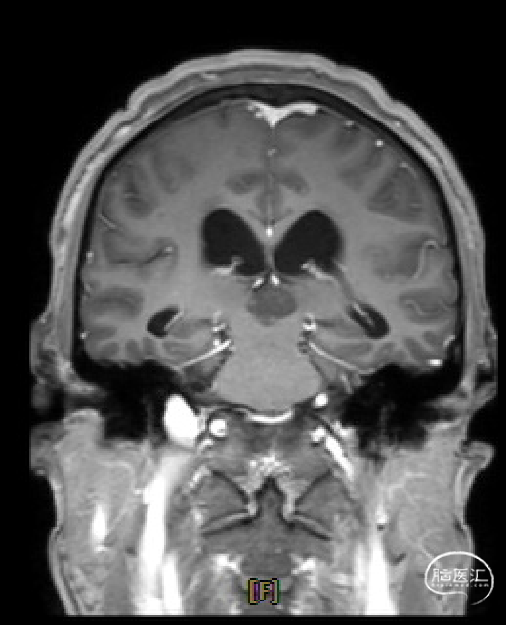

患者5年前无明显诱因出现阵发性头晕,无明显头痛、恶心呕吐等不适,开始未予重视,2022-7-19出现头晕加重,伴视力下降,遂于2022-7-24在当地医院行颅脑MRI提示:松果体区肿瘤伴梗阻性脑积水。

术前MRI与术后复查MRI对比